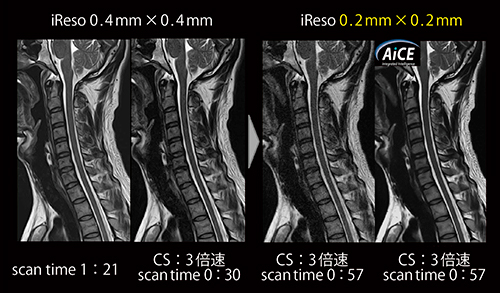

圧縮センシング法には撮像時間の短縮に加え,短縮した時間を利用した高分解能化にも期待される。しかし,高分解能化によるノイズ増加を圧縮センシングのみでデノイズしようとすると,画像劣化が顕著になってしまう。そこで,AiCEを組み合わせることで,Compressed SPEEDERによるデノイズを必要最低限にとどめることができるため,高画質化と高速化を高い次元で両立することができる(図6)。

図6 Compressed SPEEDERによる高速化